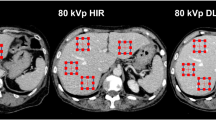

A total of 60 perfusion measurements from 14 animals were assessed. Low-dose FPA perfusion measurements (PFPA) were generated using the best dispersion delay “d = 1 s” and were related to the previously validated reference standard FPA perfusion measurements (PREF) by PFPA = 0.95 ·PREF + 0.07 mL/min/g, with a Pearson’s correlation of r = 0.94, a concordance correlation of ρ = 0.94, a root-mean-square error of 0.27 mL/min/g, and a root-mean-square deviation of 0.04 mL/min/g, as shown in Fig. 5a, with corresponding Bland-Altman analysis displayed in Fig. 5b. Additionally, the mean of the low-dose measurements was 1.51 ± 0.80 mL/min/g, while the mean of the reference standard measurements was 1.49 ± 0.80 (p = 0.691). More importantly, the \( {\mathrm{CTDI}}_{\mathrm{vol}}^{32} \) and SSDE of the low-dose FPA perfusion protocol were found to be 9.2 mGy and 14.6 mGy, respectively, corresponding to an effective dose and size-specific effective dose of 2.1 and 3.3 mSv, respectively, as estimated using the craniocaudal coverage of 16 cm and an adult chest conversion factor of k = 0.014. Perfusion maps were also generated to compare the spatial distribution of low-dose FPA perfusion measurements to the corresponding reference standard FPA perfusion measurements, as shown in Fig. 6.

Quantitative voxel-by-voxel first-pass analysis (FPA) perfusion maps. Low-dose rest (top left) and stress (top right) FPA perfusion maps are displayed as compared to reference standard retrospective rest (bottom left) and stress (bottom right) FPA perfusion maps. The color bar indicates myocardial perfusion in mL/min/g.